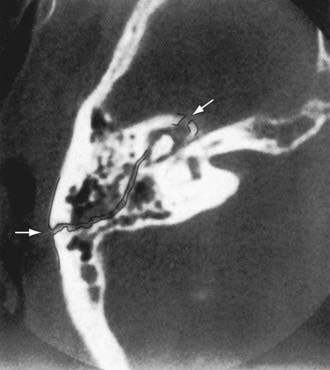

Children are particularly prone to basilar skull fractures, which usually involve the temporal bone. Temporal bone trauma should be considered in head injuries, and the status of the ear and hearing should be evaluated. Temporal bone fractures are divided into longitudinal (70-80%), transverse, and mixed. Longitudinal fractures (Fig. 634-1) are commonly manifested by bleeding from a laceration of the external canal or tympanic membrane; postauricular ecchymosis (Battle sign); hemotympanum (blood behind an intact TM); CHL resulting from TM perforation, hemotympanum, or ossicular injury; delayed onset of facial paralysis (which usually improves spontaneously); and temporary CSF otorrhea or rhinorrhea (from CSF running down the eustachian tube). Transverse fractures of the temporal bone have a graver prognosis than longitudinal fractures and are often associated with immediate facial paralysis. Facial paralysis might improve if caused by edema, but surgical decompression of the nerve is often recommended if there is no evidence of clinical recovery and facial nerve studies are unfavorable. If the facial nerve has been transected, surgical decompression and anastomosis offer the possibility of some functional recovery. Transverse fractures are also associated with severe SNHL, vertigo, nystagmus, tinnitus, nausea, and vomiting associated with loss of cochlear and vestibular function; hemotympanum; rarely, external canal bleeding; and CSF otorrhea, either in the external auditory canal or behind the TM, which can exit the nose via the eustachian tube.

Figure 634-1 High-resolution axial CT of uncomplicated longitudinal fracture (arrows). A hematoma is present. The course of the fracture has been touched.

(From Schubiger O, Valavanis A, Stuckman G, et al: Temporal bone fractures and their complications: examination with high resolution CT. Neuroradiology 28:93–99, 1986.)